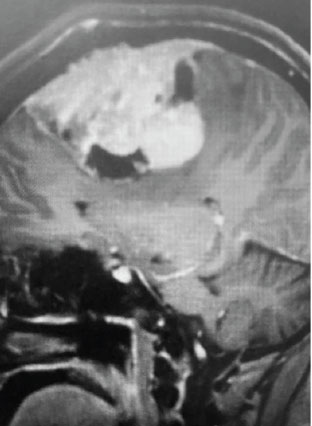

Fig 1. A) Pre-operative, post-contrast, coronal MRI. Arrow points to tumor involvement in the superior sagittal sinus.

Meningiomas that involve the superior sagittal sinus: Sometimes convexity or falx meningiomas will grow into the superior sagittal sinus. Sometimes the sinus can become completely occluded. Usually this occurs over many years, and as such, the brain has time to develop venous collaterals. So, while in a normal person, sudden occlusion of the superior sagittal sinus could lead to venous infarction or death, the very gradual occlusion that can be seen with meningiomas, does not lead to these problems. Also, if the sinus is filled with tumor and completely occluded, it can usually be safely removed at that segment.

This is a 55 year old right-handed woman who was having progressive balance problems. MRI with and without contrast demonstrated a 7 cm partly cystic meningioma involving the left frontal convexity and falx, and encasing the superior sagittal sinus. There was also tumor involvement of part of the convexity skull.